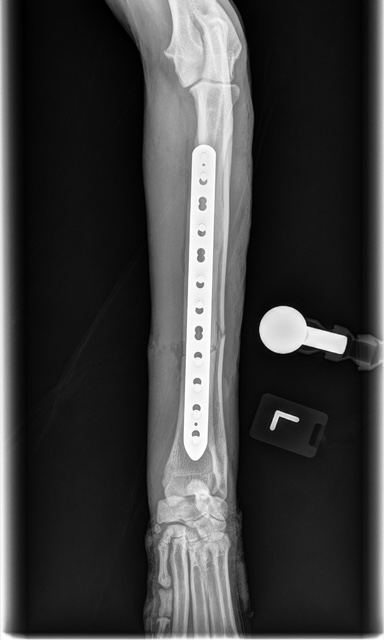

Fracture Repair

We provide surgical fracture repair for many types of broken bones. Treatment plans are individualized based on the location and complexity of the fracture, your pet’s age and size, and overall health.

Large Dog Radius Fracture Before

Large Dog Radius Fracture After #1

Large Dog Radius Fracture After #2